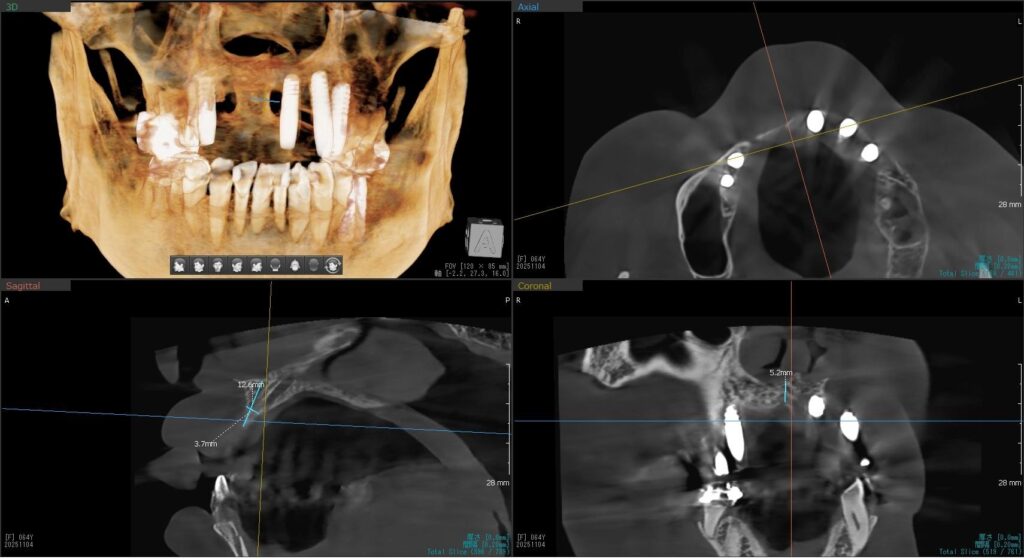

今回の患者様はインプラント植立を希望され、右上1番目・2番目の2本の植立が決まりました。

しっかりとインプラント埋め込まれた後は、動揺がないか、噛んだ時に当たらないかなどを確認して、最後にパノラマ写真を撮影して今回のオペは終了となりました。